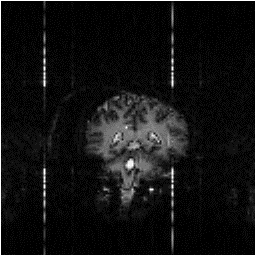

These methods were applied to a test fMRI data set of 64 volume images of a phantom and of a head, acquired over a time of 8 minutes. The first order phase correction method used was one where the signal intensity in the ghost region was minimised by applying the correction shown in equation 4.2. The Bruder correction and the two forms of the Hu correction were applied, such that one correction map was calculated, based on the first image in the set, and the same map applied to all images. Reference scans were also acquired at the end of the experiment in order to produce a correction map for every image, that was a linear interpolation between that for the first and that for the last. The graphs shown in Figure 4.10 show how well each technique corrected the ghost. The striking feature of these plots is that many of the methods, in particular the Hu correction without broadening, made the ghosting worse. This occurs in the columns in the image where the external r.f. interference is at its worse. The effect that this has on the image is shown in Figure 4.11a. Again the Buonocore method works the best in this situation for both head and ghost data. However, this technique does not always work, as is shown in Figure 4.11b. Since this correction is only based on those lines in which the ghost and image do not overlap, the method has failed where the signal intensity in the central rows is low. An appropriate choice of threshold can prevent low signal intensity having an adverse affect on image quality, but this highlights the care that must be used in applying any technique.

Figure 4.10. Ratio of image intensity within the ghost to within the object for the five correction methods explained in the text, based on six images (128 x 128 matrix size) each with slightly different ghosting.

(a) (b)

Figure 4.11. Examples of the failure of two correction methods to remove the N/2 ghosting. (a) Hu correction without broadening, (b) Buonocore correction.